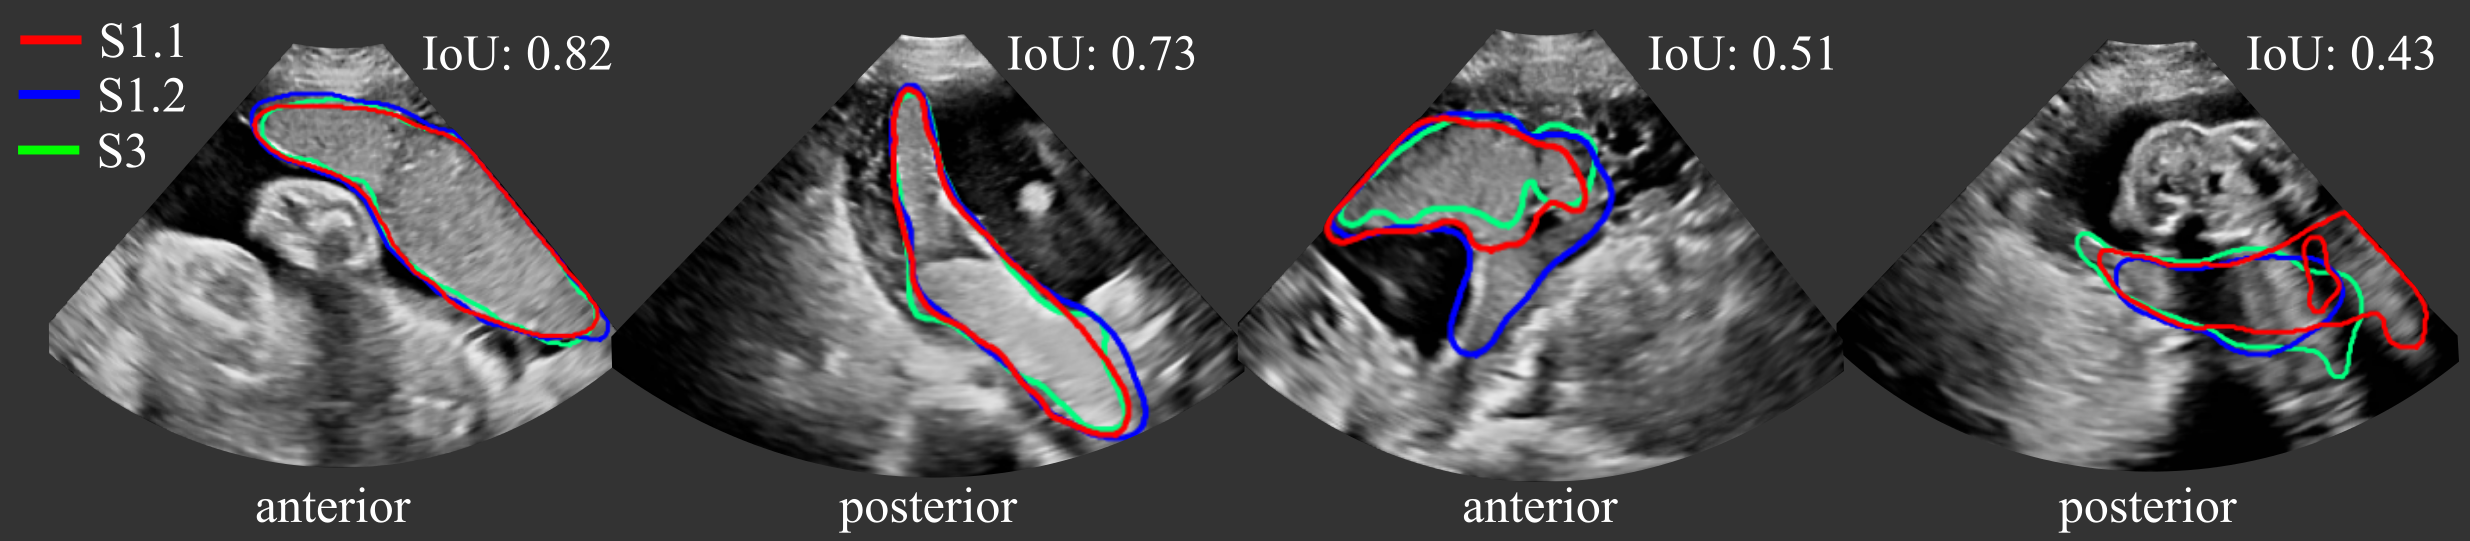

The segmentation performance of the different models measured by Dice, IoU, ASD and RHD are reported in Table 2 and representative segmentations comparing InD and OoD examples are shown in Fig. 4 with further examples in Fig. 11. Results using different training and validation sets suggest that anterior and posterior placentas represent two different distributions in the data. The baseline UNet trained on set A (only anterior) achieves a high Dice score of for the InD test set (anterior), but performs poorly on the OoD set (posterior) with a Dice score of . When trained on set P (only posterior), the Dice score for the InD set (posterior) is , and for the OoD set (anterior). The performance on the OoD sets is reduced with a higher standard deviation, indicating that the sets A and P alone are not representative enough for the segmentation of all types of placenta. These results confirm also that it is easier to segment anterior placentas, which achieve both a higher InD and OoD Dice score. The same trend is observed for the other performance metrics (IoU, ASD, RHD) and models (TUNet, MTUNet, TMTUNet).

Figure 4 visualizes examples comparing the segmentation when the images was InD or OoD data. Multi-task models, especially TMTUNet (row 4) show a more robust performance with respect to OoD data. For example, UNet tries to segment a posterior placenta in OoD of example 2 and an anterior placenta in OoD of example 3. Also, MTUNet and TMTUNet are more robust to image artifacts, such as shadows, which is shown in InD of example 3. Further examples can be found in Fig. 11 in the appendix.

We investigated the inter- and intra-observer variability for the manual annotation of placental tissue in 3D US. In each fold, we use a subset of the test set, for which three manual annotations are available, as described in Section 3.2. Figure 6 (a) shows the agreement of the segmentations as measured by Dice. We compared the agreement between manual raters S1.1 and S1.2 (intra-variability) and S1.1 and S3 (inter-rater variability), and Figure 7 shows examples with best and worst intra- and inter-observer agreement. In addition, we assess the agreement between manual and automatic segmentations (UNet and MTUNet), which are summerized under the term intra with reference S1.1 and inter with reference S3 in Fig. 6.

Comparing the agreement between manual annotations (plain white bars in Fig. 6), we observe that the intra-observer agreement is higher than the inter-observer agreement for all measures. The difference is statistically significant for anterior placentas with a moderate effect size and for posterior placentas with a strong effect size, denoted by one and two asterisks, respectively, above the bar for inter-rater agreement.

This suggests that the manual annotation of the placenta in US is a subjective task. In all cases and for all measures, the agreement in segmenting posterior placentas is smaller than in anterior placentas, emphasizing that the segmentation of posterior placentas is more ambiguous, possibly due to image artifacts. This is in line with the observation of the previous experiment, that the automatic segmentation models perform worse for posterior than for anterior placentas.

The intra-observer comparison of anterior placentas achieved the best agreement with a Dice of , an IoU of , an ASD of and a RHD of . These values can be therefore interpreted as an upper bound and the range between inter- and intra-observer agreement as the desired performance of any automatic segmentation model. For anterior placentas, both the baseline model UNet and our best performing model MTUNet, as selected in the previous experiment, lie within intra- and inter-rater variability with no significant difference () between the segmentation agreements. For posterior placentas, there is a statistically significant difference (with a moderate effect size) for the baseline model UNet, but not for MTUNet. The multi-task approach increases the performance and reduces the variance for all measures. The same trend is observed for IoU, ASD and RHD (see Fig. 13 in the appendix).